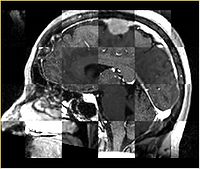

Checkerboard

Builds a "puzzle-piece" collage of blocks from both images, alternating between the two. Helpful if the two images are from different modality or have different contrast. Continuity of edges becomes very apparent on such images.

Case10-FLIRT-saggital.jpg